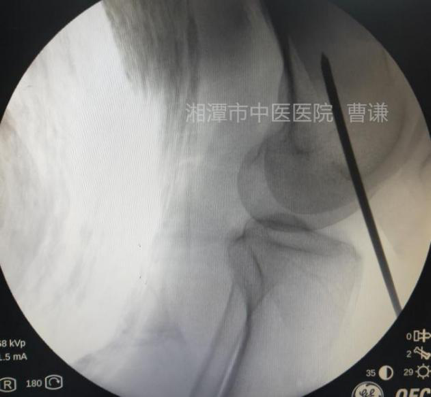

麻醉生效后,常规消毒铺无菌巾,先在体表放置一根克氏针透视,确定骨折端适宜钢丝捆扎的部位。

透视见钢丝逐渐拧紧并使骨折端靠近复位。